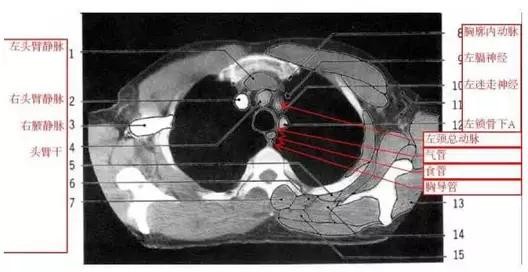

详尽的胸部CT影像示意图

胸部的CT是通过X线计算机体层摄影(CT)对胸部进行检查的一种方法。正常胸部CT层面较多,每一层面结构所表现的图像不同。下面是胸部CT图文示意图,可帮助临床医生详细了解CT结构。我们一起来看一下吧。